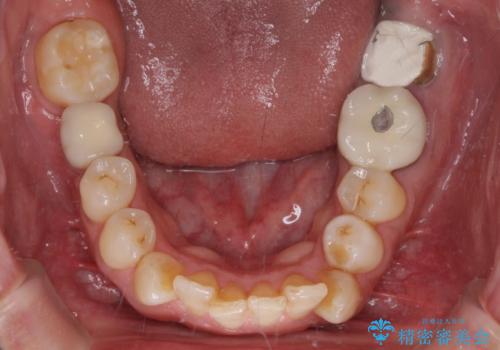

- 近医にて奥歯の抜歯が必要と言われたとのことで来院された患者様です。

診査の結果、歯が破折しており、抜歯が必要な状態でした。

最後方歯であるため、入れ歯かインプラントかどちらかの補綴治療を行うこととなりますが、ご希望によりインプラント補綴治療を行うこととしました。

インプラントにはストローマン社のSLActiveを使用し、埋入から補綴までおよそ3か月と、短期間で治療を進めることができました。